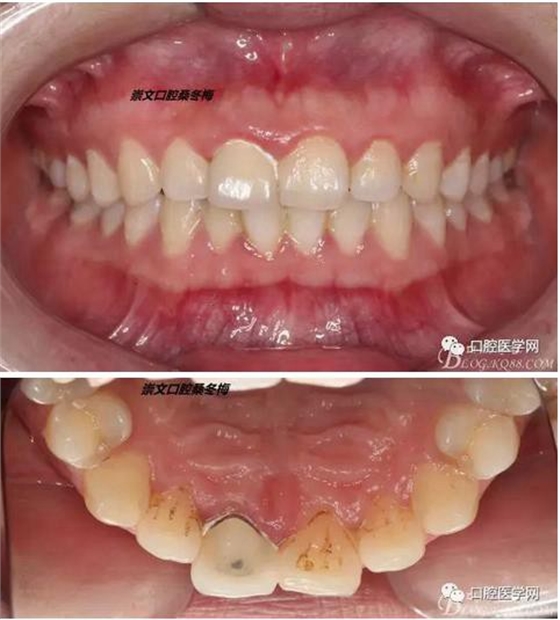

術(shù)前X線片

輔助檢查:X線見(jiàn)根尖區(qū)輕低密度影像,根尖1/3見(jiàn)根充物密實(shí)恰填,根管上2/3見(jiàn)折斷纖維樁,與根管密實(shí)。